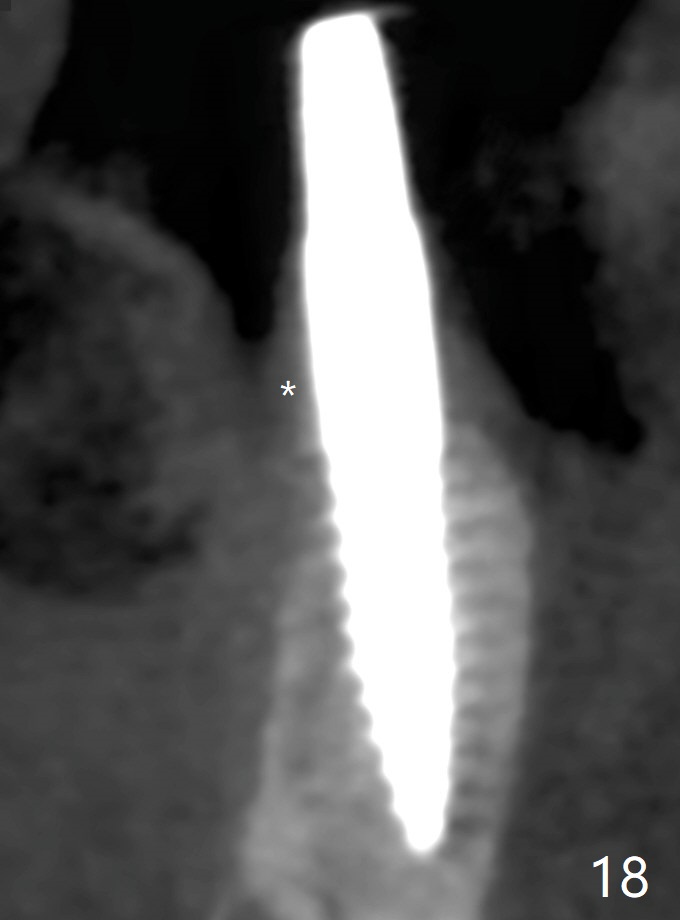

The buccal gingiva is recessive at #29 and 30 (Fig.1). Incision reveals buccal implant thread exposure with circum-ferential granulation tissue (Fig.2 *). Immediate post implant removal at #29, osteotomy is initiated lingual (Fig.3 (intraop CT, coronal section) ). A smaller and shorter implant (3x12 mm vs. 3.5x13 mm) is placed away from buccal (Fig.4 B, 5).

The implant at #30 was also buccally placed (Fig.6,7) and should be corrected in the same manner (Fig.7 green). Due to the bone being harder in the molar region, a smaller and shorter implant (4x11 mm vs. 5x13 mm) shifts slightly buccally while being placed (Fig.8,9). Since primary stability is lower (<20 Ncm vs. 35 Ncm associated with the implant #29), an abutment is not placed, which may be favorable to healing, but it is difficult to achieve primary closure. After bone graft (Fig.9 *) and 2 layers of PRF, Cytoplast is placed. Cytoplast appears to be exposed buccally (Fig.10 <) and occlusally (Fig.11 ^) asymptomatic 9 days postop. Exposure of Cytoplast is more distinct without sign of infection 15 days postop (Fig.12). The patient returns with chief complaint of "foul smell" 7 weeks postop (coronavirus lockdown). Although the Cytoplast exposes more (Fig.13 (* exposed; @ unexposed)), the underlying gingiva remains healthy (Fig.14). While the bone height decreases at #29, the bone density at #30 increases 4.5 months postop (Fig.15). The gingiva heals. The implant at #30 is uncovered 6 months postop. The lingual plate has to be removed for the uncover, while the coronal end of the buccal one is missing. No bone graft is added. When the 4.5x4 mm healing abutment is removed 6.5 months postop, the buccal plate looks concave at #30 (Fig.16' *). The buccal plate looks thin at #29 with a cotton roll placed buccally (Fig.16 R). The lingual plate at #29 is coronal to the buccal one (Fig.17). The buccal gingiva at #29 is quite long (Fig.18). The coronal buccal plate appears to be missing (Fig.19 >), which will be watched. A 4.5x7.5(4) mm cemented abutment is torqued (Fig.20).